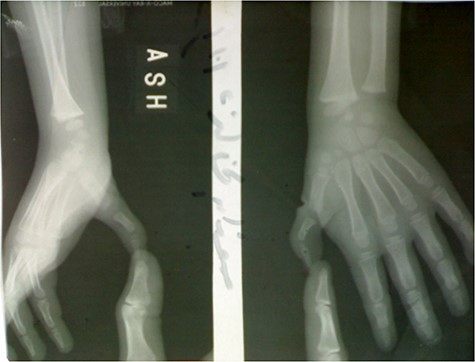

X-ray imaging of the right hand showed small-sized bones of the right thumb including first metacarpal and phalanges, it also showed the good alignment of the CMC and MCP joints.

The following movements: flexion, adduction and opposition were within normal.

Neither stiffness nor instability in interphalangeal (IP) or metacarpophalangeal (MCP) joints was observed (Fig. 2).